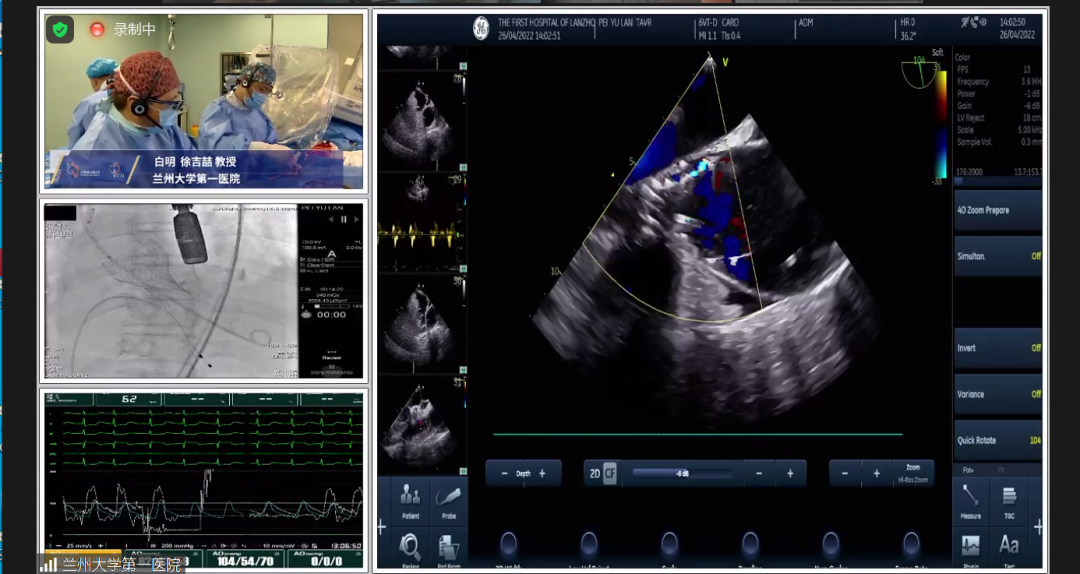

术前超声心动图:

主动脉瓣狭窄(重度,跨瓣平均压差65mmHg),并关闭不全(中度);瓣环直径2.3cm,有效开口面积0.35cm²;主动脉硬化并主动脉瓣钙化,升主动脉内径5.1.cm; AV 5.0m/s,EF 41%。

根据测得的瓣环直径,结合患者二叶式主动脉瓣,瓣叶见钙化,以及畸形的有效开口,术中决定采用Evolut PRO 23mm瓣膜。递送系统顺利过弓跨瓣,球囊预扩后目标深度开始释放,得益于可回收设计,术中再回收进行一次位置调整,最终目标位完美释放,瓣膜立即工作,展开形态良好,无冠脉阻挡,无传导阻滞发生,术后压差<10mmHg,血流动力学稳定,手术圆满成功。